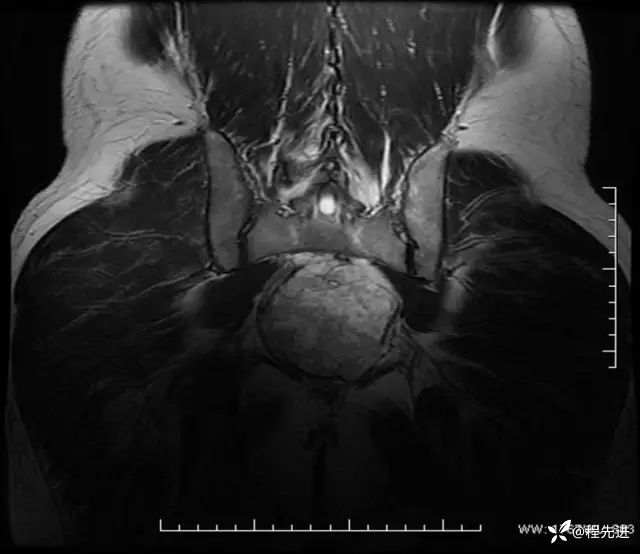

T2冠状位: